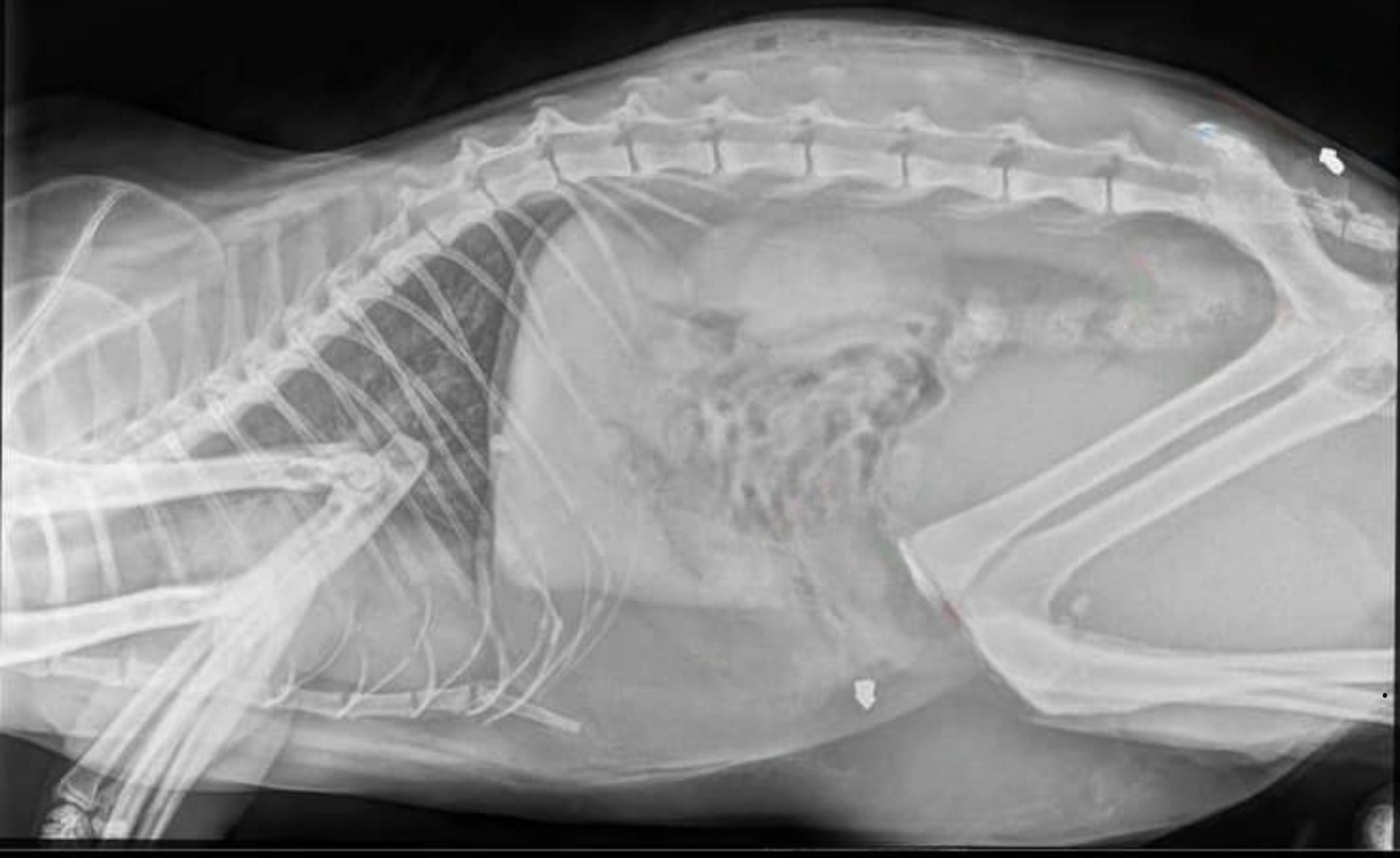

- W weekend nasz kot został kilkukrotnie postrzelony z wiatrówki. Grzybkowaty śrut jest w pobliżu kości krzyżowej oraz w otrzewnej. Poza tym ma jeszcze ranę na grzbiecie, najprawdopodobniej po nietrafionym strzale. Bardzo proszę o wiadomość jeśli ktokolwiek ma jakieś informacje w tej sprawie lub słyszał strzały w miniony weekend - opowiada pani Aleksandra, mieszkanka Kłodawy.

Sprawa została zgłoszona na policję. We środę 5 marca kot przeszedł operację pod narkozą. Na szczęście wszystko przebiegło pomyślnie i zwierzę przeżyło. Niestety nie jest to pierwszy tego typu przypadek w gminie Kłodawa. Dużo mniej szczęścia miał kot z Wojcieszyc, który w listopadzie 2024 roku został zastrzelony przy pomocy wiatrówki o czym portal gorzowianin.com informował „Ktoś zastrzelił kota z wiatrówki. Wyznaczono nagrodę za wskazanie sprawcy”.